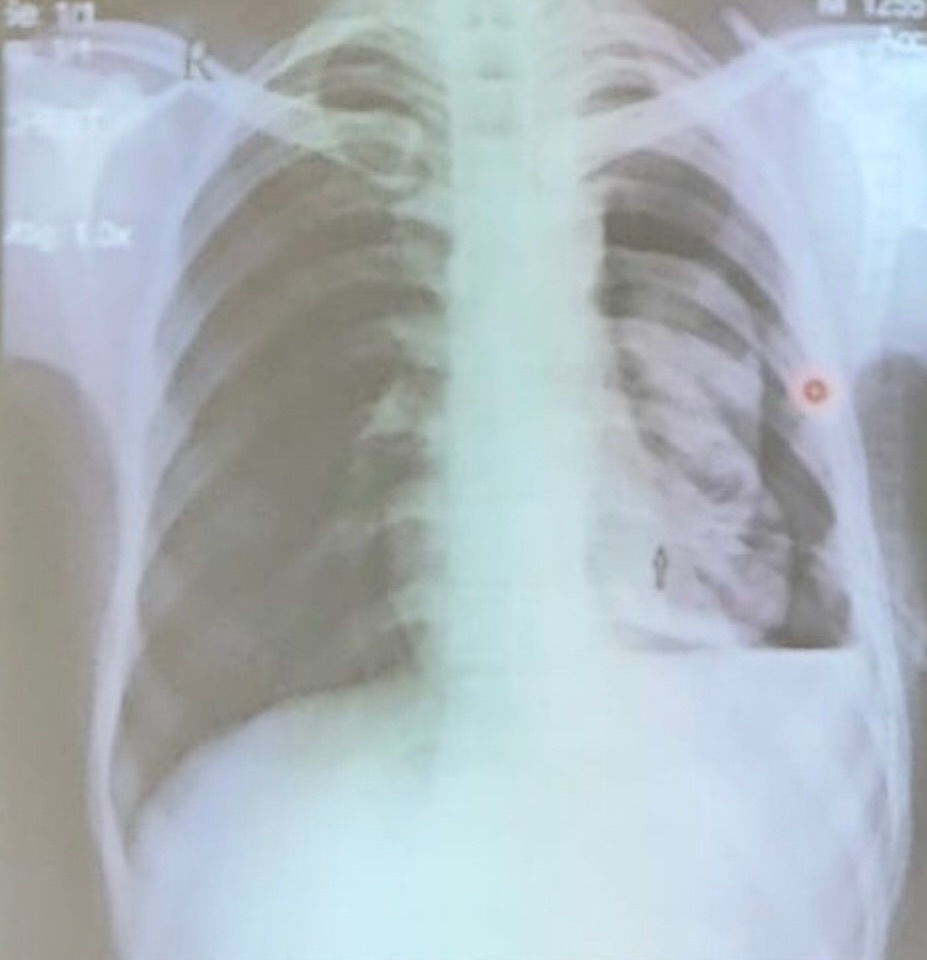

neumonía